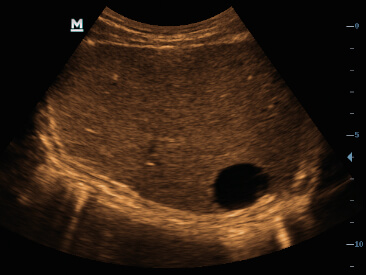

Im├Īgenes cl├Łnicas